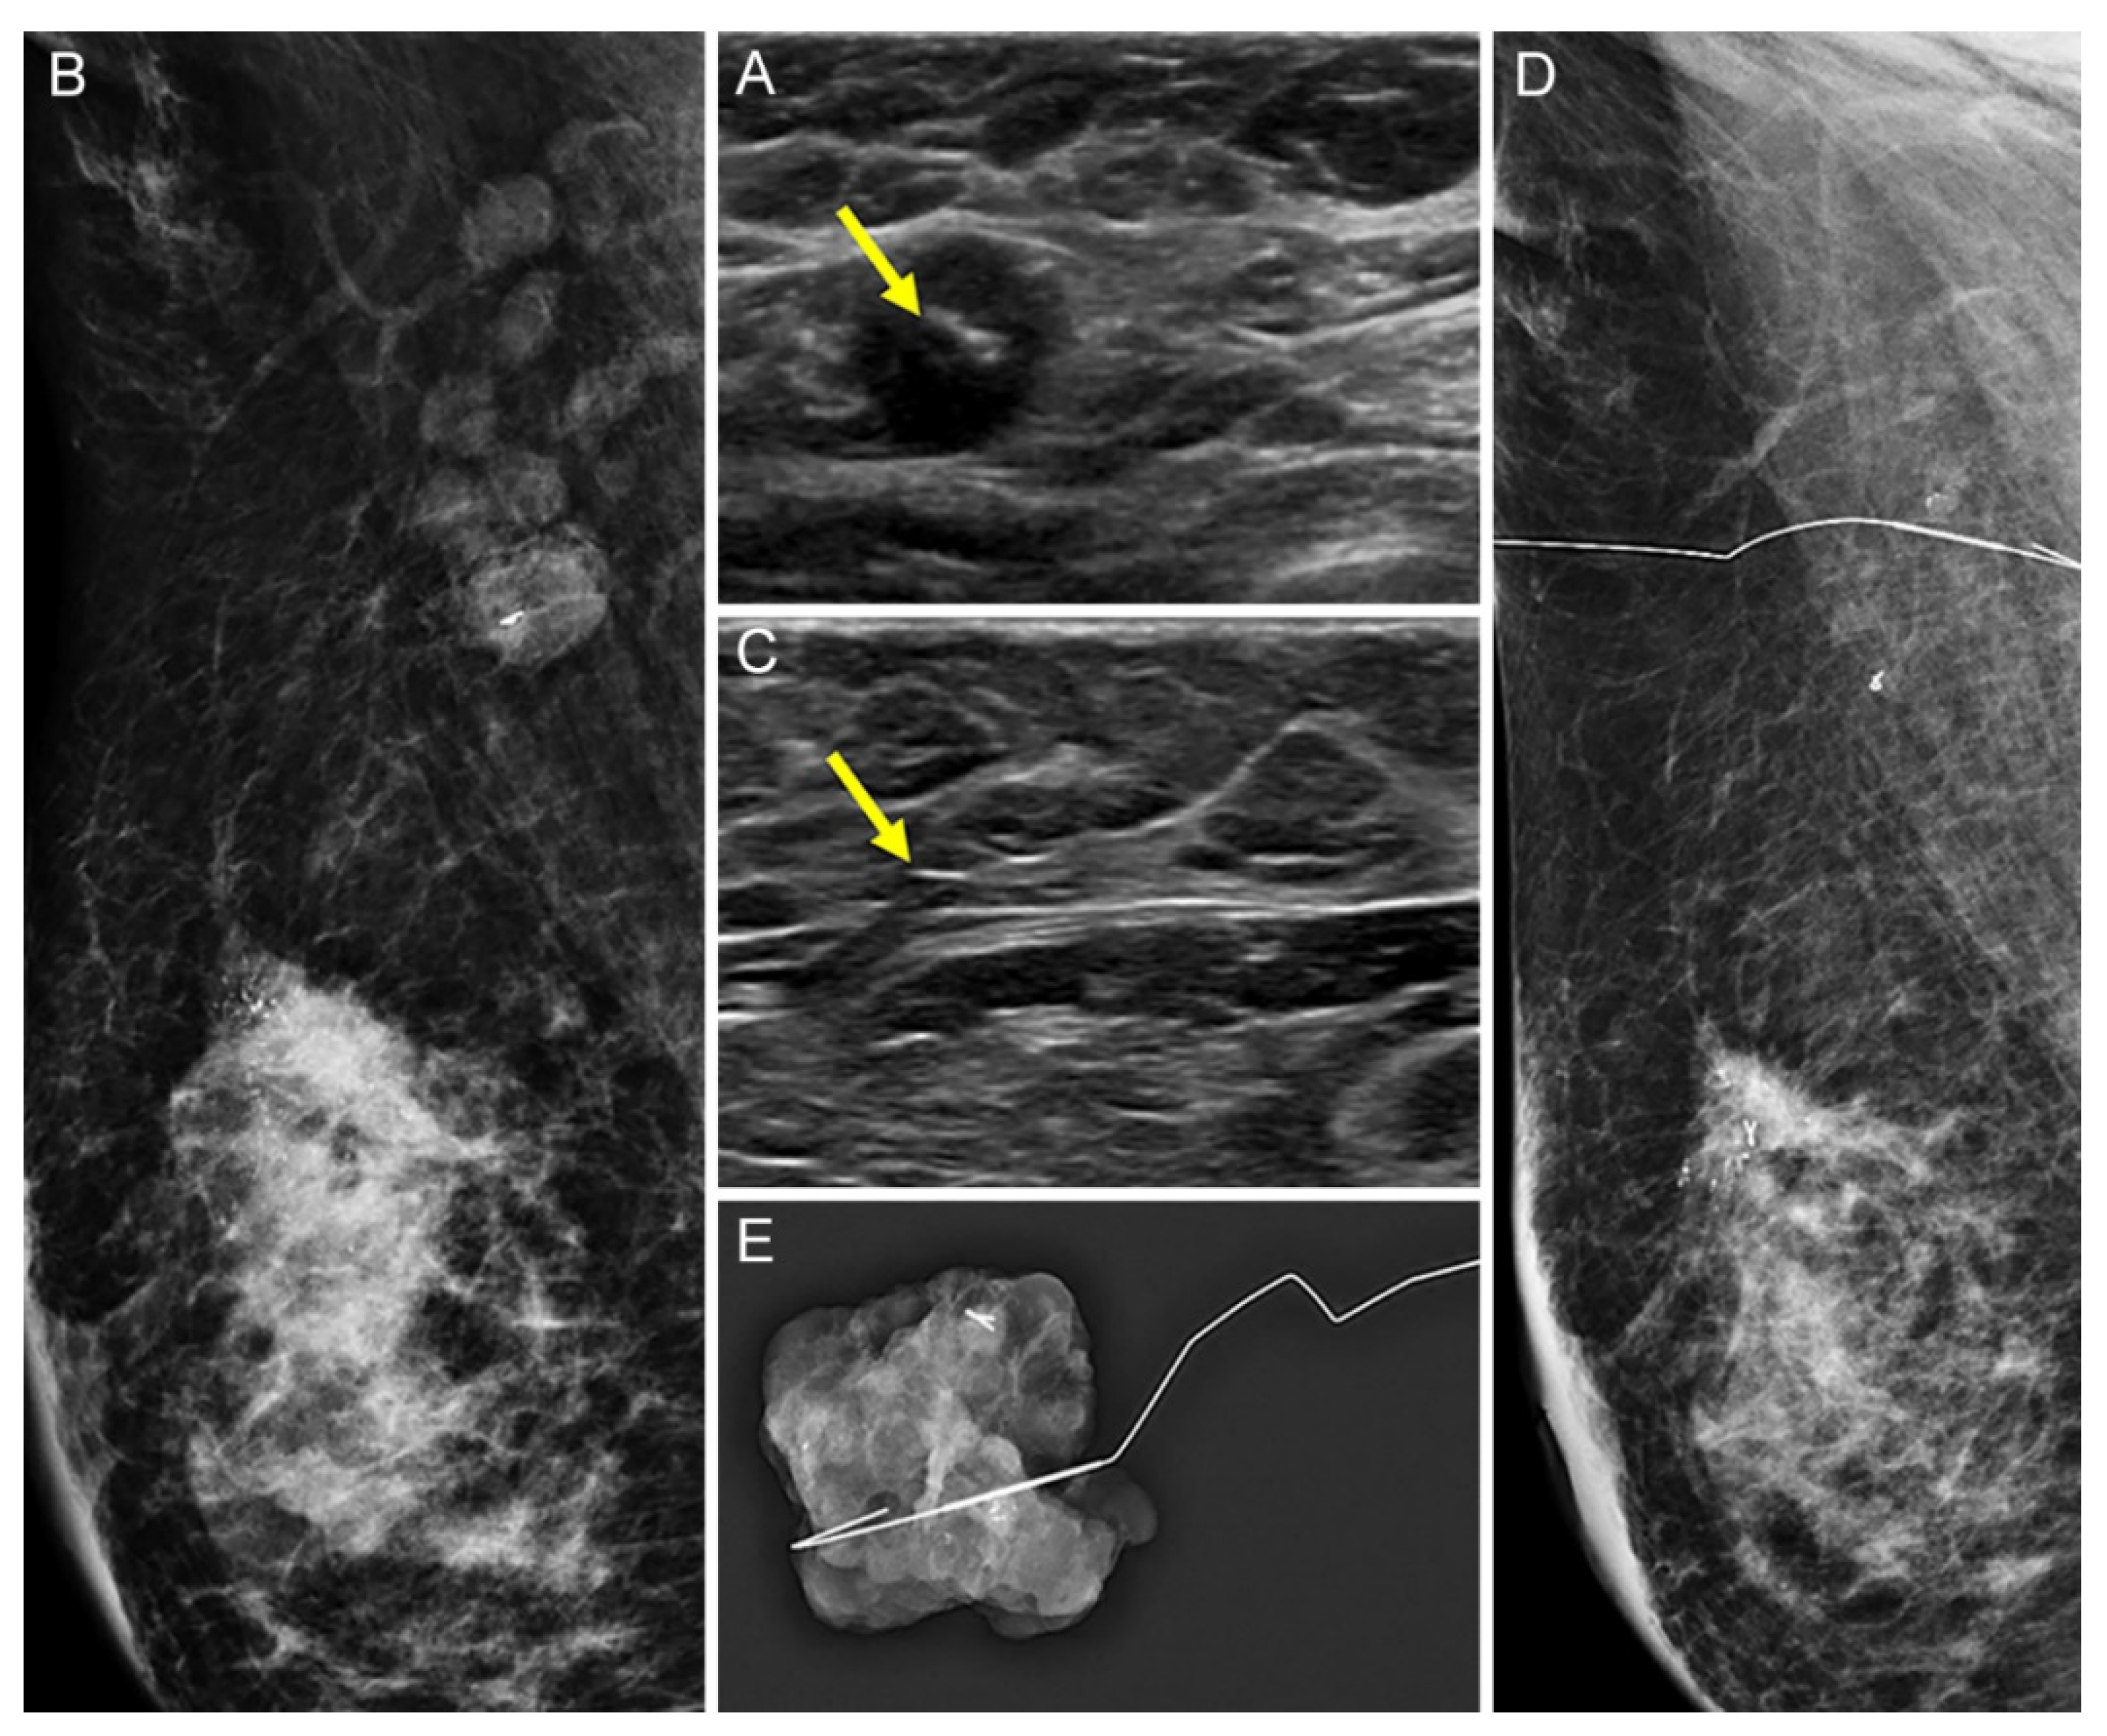

2.2. Tissue Marker Insertion for Axillary Lymph Nodes before NAC

2.3. Localization of Tissue Marker-Inserted Axillary Lymph Nodes after NAC

3.1. Comparison of the US Visibility between the Two Tissue Markers after NAC